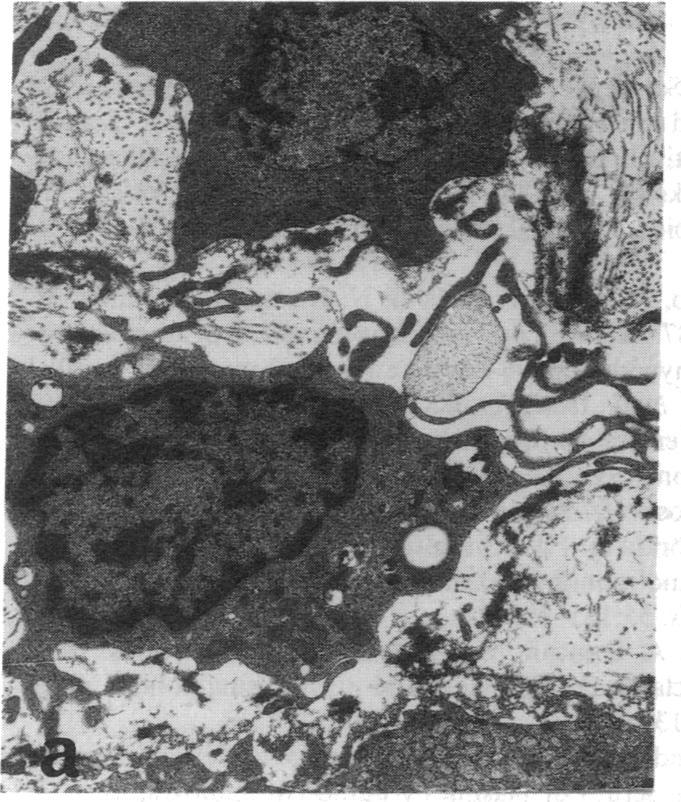

The effect of the antioxidant butylated hydroxytoluene (BHT) on the accumulation of intimal smooth muscle cells (SMC) and development of intimal thickening after balloon catheter injury of the aorta were studied in rabbits with dietary-induced hyperlipidemia. Two sets of New Zealand White rabbits (eight rabbits in each group) were fed either 0.25% cholesterol or 0.25% cholesterol/1% BHT for a total of 6 wk. Serum lipid levels did not differ between the two groups. 3 wk after the start of the study, a balloon injury of the aorta was performed, after which the rabbits were kept on their respective diets for another 3 wk. After this period of time, the rabbits were killed and their aortas were investigated. The BHT-treated rabbits had only one fourth of the intimal thickness (P < 0.0001) and half the number of SMC/mm intima (P < 0.001), as compared to the rabbits fed only cholesterol. There was also a lower number of macrophages in the BHT-treated group. T lymphocytes were present in the intima of cholesterol-fed rabbits, whereas no such cells could be identified in the BHT-fed animals. There were significantly lower levels of autooxidation products of cholesterol (7-oxocholesterol, cholesterol-5,6-epoxide, and 7 beta-hydroxycholesterol) in the aortas of BHT-treated rabbits, P < 0.001. In conclusion, the antioxidant BHT effectively inhibited the accumulation of intimal SMC and the development of intimal thickening of the aorta in hypercholesterolemic rabbits after a balloon catheter-induced injury. These results indicate that antioxidants may modify intimal response to injury.

在饮食诱导的高脂血症兔中,研究了抗氧化剂丁基羟基甲苯(BHT)对主动脉球囊导管损伤后内膜平滑肌细胞(SMC)积聚和内膜增厚发展的影响。两组新西兰白兔(每组8只)分别喂食0.25%胆固醇或0.25%胆固醇/1%BHT,共6周。两组血清脂质水平无差异。研究开始3周后,对主动脉进行球囊损伤,之后兔子继续各自的饮食3周。此段时间后,处死兔子并检查其主动脉。与仅喂食胆固醇的兔子相比,经BHT处理的兔子内膜厚度仅为其四分之一(P<0.0001),内膜中SMC/mm数量为其一半(P<0.001)。BHT处理组巨噬细胞数量也较少。在喂食胆固醇的兔子内膜中有T淋巴细胞,而在喂食BHT的动物中未发现此类细胞。经BHT处理的兔子主动脉中胆固醇的自氧化产物(7-氧胆固醇、胆固醇-5,6-环氧化物和7β-羟基胆固醇)水平显著较低,P<0.001。总之,抗氧化剂BHT有效抑制了高胆固醇血症兔在球囊导管诱导损伤后内膜SMC的积聚和主动脉内膜增厚的发展。这些结果表明抗氧化剂可能会改变内膜对损伤的反应。